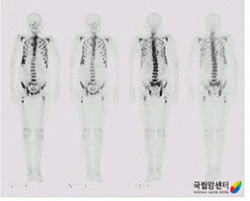

다발성 전이가 있는 전립선암의 골스캔 소견

2009.08.24